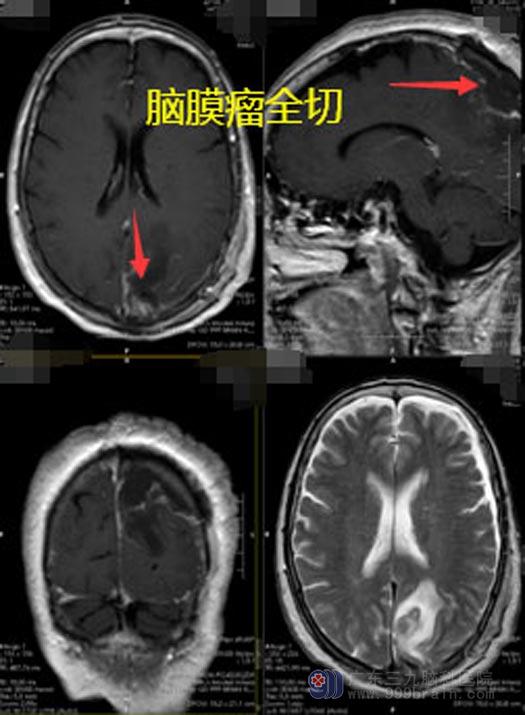

进一步完善相关的检查,明确张奶奶是左侧顶部占位性病变,考虑良性肿瘤。神经外五科鲁明团队很快就制定了手术方案,在全麻下行左侧顶部肿瘤切除术,肿瘤镜下全切,术中出血量很少。

▲手术后